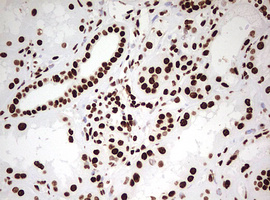

Immunohistochemical staining of paraffin-embedded Carcinoma of Human liver tissue using anti-HNRNPM mouse monoclonal antibody. (Heat-induced epitope retrieval by 10mM citric buffer, pH6.0, 120°C for 3min, M06017-2)